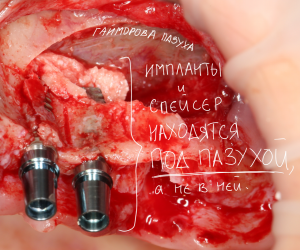

Распространено ошибочное мнение, что синуслифтинг – это операция в гайморовой пазухе. На деле, она проводится не «в», а «под» ней, что также следует из названия (рис. 1,2).

Рисунок 1, 2. Синуслифтинг – операция не «в-», а «под» гайморовой пазухой.